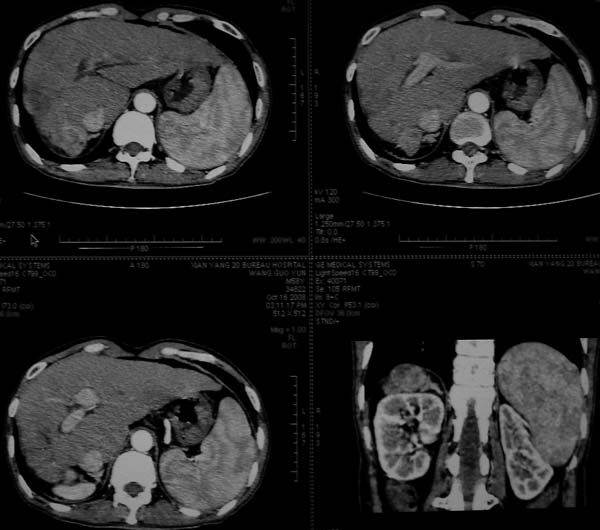

标题: CT16292:男,53岁,上腹部不适2月,B超发现肝内占位病变。 [打印本页]

标题: CT16292:男,53岁,上腹部不适2月,B超发现肝内占位病变。

符合肝ca增强,\"快进快出\";肝叶比例失常,右叶萎缩,肝裂增宽,脾大,肝硬化可能.

肝脏体积变小,肝裂增宽,分布异常,肝尾叶增大,脾肿大,考虑肝硬化可能性大,右肝病灶呈现早期充盈,延迟强化考虑肝内胆管细胞癌可能,不除外血管瘤

肝叶比例失调,左叶增大,肝裂增宽,脾脏增大,门脉增宽,肝右叶包膜下多发结节样阴影,增强虽说强化幅度不大,但还是符合快进快出特点;考虑肝硬化、脾大、结节型肝癌。胆管细胞癌多有延时强化、肝包膜凹陷征、周围胆管扩张等特点,本例明显不符;故不考虑。